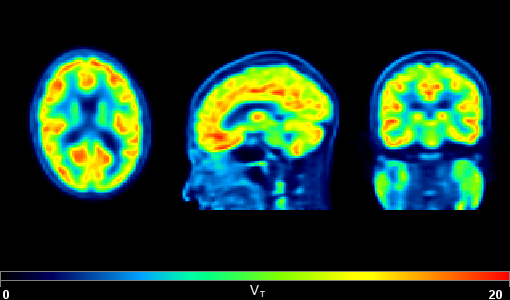

PKIN Kinetic Modeling

PXMOD Pixel-wise Modelling

Application of mathematical models in every pixel with workflow-based quantitative parametric maps.

Includes over 30 blood-based and reference tissue models for dynamic PET data, and several models for fMRI data such as DWI, DTI, pCASL, resting state and 4D flow